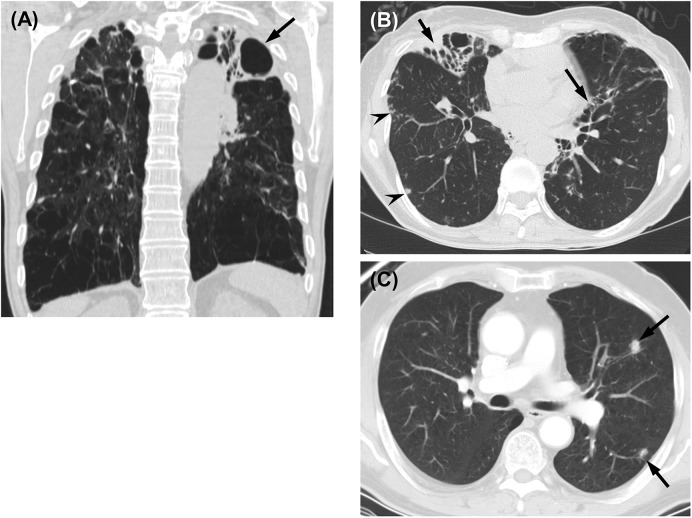

Among 54 patients who met the ATS/IDSA diagnostic criteria for NTM lung disease, 41 (76%) received antibiotic treatment and the median duration from diagnosis to initiation of treatment was 1.7 months (0.3–3.8 months). The remaining13 (24%) patients with mild symptoms underwent regular follow-up without antibiotic treatment for a median time of 26.5 months (IQR, 8.8–35.3 months) and a median of 8.0 (IQR 3.0–11.5) sputum cultures were obtained during follow-up. Based on the chest radiography and HRCT findings in all 54 patients, 24 (44%) patients manifested the fibrocavitary form, 17 (32%) had the nodular bronchiectatic form, and 13 (24%) exhibited an unclassifiable form of M. kansasii lung disease. The diverse radiographic findings are shown in Fig 1.

Fig 1. Diverse patterns in images of M. kansasii lung disease.

(A) A 64-year-old man with M. kansasii lung disease. A coronal thin-section (2.5-mm thickness) CT scan shows a thick-walled cavitary lesion (arrow) with consolidation in the left upper lobe. Severe pulmonary emphysema is also observed. (B) A 66-year-old woman with M. kansasii lung disease. A transaxial thin-section (2.5-mm thickness) CT scan obtained at the basal trunk level shows bronchiectasis (arrows) and multiple branching centrilobular nodules, the so-called tree-in-bud pattern (arrowheads), in both lungs. (C) A-77-year-old man with M. kansasii lung disease. A transaxial (5-mm thickness) CT scan obtained at the level of the left main bronchus shows two nodules in the left lung (arrows). Lung biopsy revealed chronic granuloma; M. kansasii was isolated from the bronchial washing fluid.